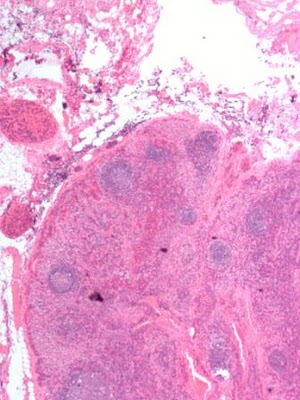

O pâncreas é composto, na sua maior parte, por células exócrinas, que produzem as enzimas digestivas e que estão organizadas em grupos que comunicam entre si por pequenos canais. É por esses canais que os sucos circulam até desembocarem num caminho principal - o canal pancreático, que conduz ao duodeno. Antes, porém, junta-se-lhe o canal biliar, que transporta a bílis desde o fígado e a vesícula.

Existem ainda no pâncreas pequenas ilhas de células endócrinas - os ilhéus de Langerhans - que segregam a insulina e o glucagon, libertando-as na corrente sanguínea, juntamente com uma outra hormona, a somatostatina, que regula a secreção da insulina e glucagon.